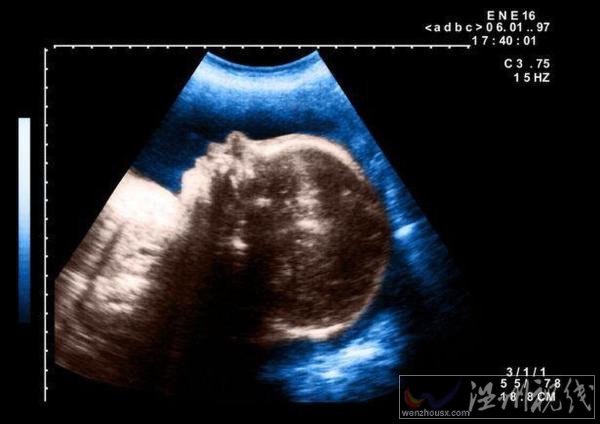

10月7日,埃及一名孕婦產(chǎn)下一個(gè)獨(dú)眼嬰兒,這個(gè)孩子在出生幾天后死亡。埃及嬰兒一只眼睛一時(shí)引起不少人關(guān)注,這名醫(yī)生猜測,可能是嬰兒在子宮內(nèi)受到放射物影響導(dǎo)致的畸形。

據(jù)悉,當(dāng)時(shí)這名醫(yī)生在被這個(gè)孕婦做檢查時(shí),就發(fā)現(xiàn)她懷的這個(gè)孩子是一個(gè)嚴(yán)重畸形兒,但是沒想到會是這樣的。這個(gè)嬰兒出生時(shí),只有一只長在中間的眼睛,在眼睛下面就是一張嘴巴。

醫(yī)生在對其做完接生后預(yù)計(jì)這個(gè)孩子活不過幾天,對于孩子畸形的原因,他認(rèn)為應(yīng)該是受到放射物質(zhì)影響。